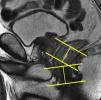

Tras el localizador inicial es recomendable realizar 3 secuencias rápidas de disparo único (single shot) ponderadas en T2 en los 3 planos para tener una mejor visión de la región a explorar y una mayor aproximación al área afectada. A continuación han de emplearse las secuencias de alta resolución FSE ponderadas en T2. En primer lugar ha de obtenerse una serie en plano sagital estricto de todo el mesorrecto que, además de aportar información para el diagnóstico (extensión cráneo-caudal del tumor y grado de infiltración), debe servir para planificar las demás secuencias con precisión. Seguidamente han de obtenerse planos perpendiculares y paralelos al eje longitudinal del recto que incluyan el mesorrecto en toda su extensión, desde el promontorio del sacro hasta el margen anal y desde el septo urogenital hasta el sacro (figs. 7 y 8). El objetivo de estas secuencias es evaluar posibles adenopatías mesorrectales y estudiar la posibilidad de aplicar implantes. Llegados a este punto, según el tercio del recto en estudio, es necesario obtener planos oblicuos directamente sobre la masa tumoral:

Han de obtenerse planos axiales oblicuos que cubran el tumor en toda su extensión y queden orientados perpendicularmente a su eje cráneo-caudal en el plano sagital (fig. 9). Las imágenes resultantes permiten evaluar el propio tumor y la afectación de la pared rectal y del mesorrecto, así como la afectación de las estructuras y órganos pélvicos.